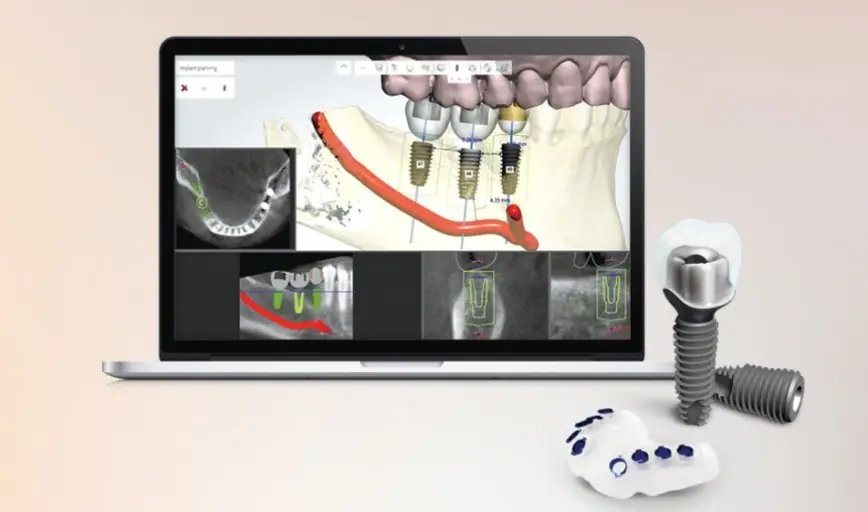

임플란트 치료를 앞두고 계신 분들이 걱정하는 부작용 문제, 사실 올바른 진단과 계획, 맞춤형 수술, 그리고 꾸준한 사후 관리가 가장 중요하다는 점을 알려드리고 싶어요. 임플란트는 단순히 치아를 심는 수술이 아니라, 앞으로의 생활과 건강까지 고려하는 치료이기 때문에, 뼈와 잇몸 상태를 꼼꼼히 살피고, 개인별 맞춤 수술이 필요하죠. 특히 뼈가 부족하거나 잇몸이 약한 분들은 보강이나 특수 임플란트가 도움이 될 수 있어요. 수술 후에는 정기검진과 올바른 구강 위생 습관이 필수입니다. 집에서도 치실이나 양치법을 잘 지키고, 정기 검진을 통해 잇몸과 뼈 상태를 체크하는 것이 부작용 방지와 오래 쓰는 비결입니다. 임플란트는 완성품이 아니라 관리품이라는 마음가짐으로 꾸준히 관리하는 것이 중요하니, 치료 전후의 철저한 준비와 관리로 건강한 치아를 오래 유지하시길 바랍니다.